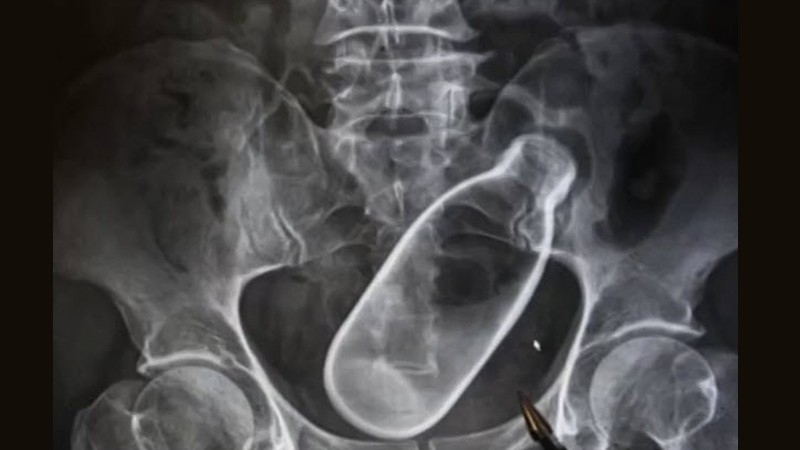

Уг хэрэг мөн л Хятадад болжээ. 2017 онд шулуун гэдэснийхээ амсарт шил хийж гацаасан нэгэн эрэгтэй түргэн тусламжаар эмнэлэгт ирсэн байна. Тэрбээр эмнэлэгт ирэхээсээ өмнө бүтэн хоёр өдрийн турш шилийг гаргаж авахаар янз бүрийн аргаар оролдсон бөгөөд үр дүнд нь шулуун гэдэс нь хавдсанаас шил хагарчээ.

Тус шил нь 7 см диаметртэй байсан бөгөөд эмч нар шилийг гараар авах боломжгүй байсан тул яаралтай мэс засал хийн биенээс нь гаргасан байна. Хагалгааны дараа өвчтөний биеийн байдал сайжирсан бөгөөд ямар ч зовуургүй эдгэжээ.